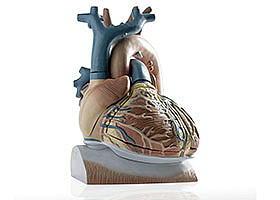

Herzmodelle zur Behandlung von Vorhofflimmern

Mit individuellen, digitalen Herzmodellen können Therapien getestet werden, um diejenige auszuwählen, die den größten Erfolg verspricht. Ein Verfahren des KIT erstellt aus klinischen Daten patientenspezifische virtuelle Abbilder des Herzens.

Ventrikuläres Fernfeld mit Katheter bestimmen

Computersystem verbessert Signale von Ablationskathetern bei Herzrhythmusstörungen durch Berechnung des ventrikulären Fernfeldes in unipolaren Elektrogrammen im Vorhof.